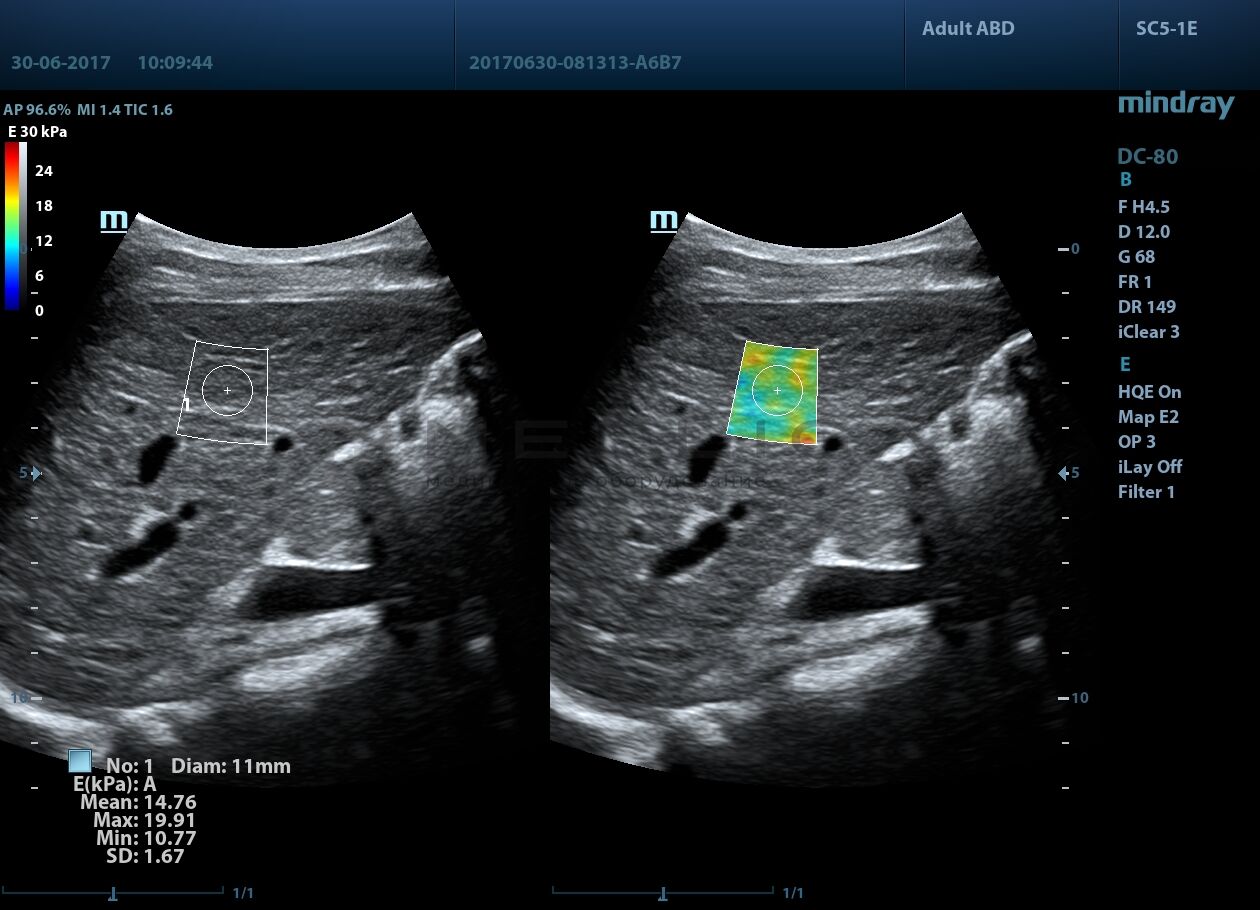

Программное обеспечение для оценки эластичности ткани методом эластографии сдвиговой волны (метод 2D-с формированием двухмерной цветовой эластограммы и количественной оценкой эластичности) на линейных и конвексных датчиках.

STE интегрирована с эксклюзивной технологией Ultra-Wide Beam Tracking от Mindray для двумерной эластографии сдвиговой волной в реальном времени. Специализированные измерительные инструменты позволяют проводить количественный анализ модуля упругости с высокой точностью.

Опция работает:

• на линейных датчиках

• на конвексных датчиках